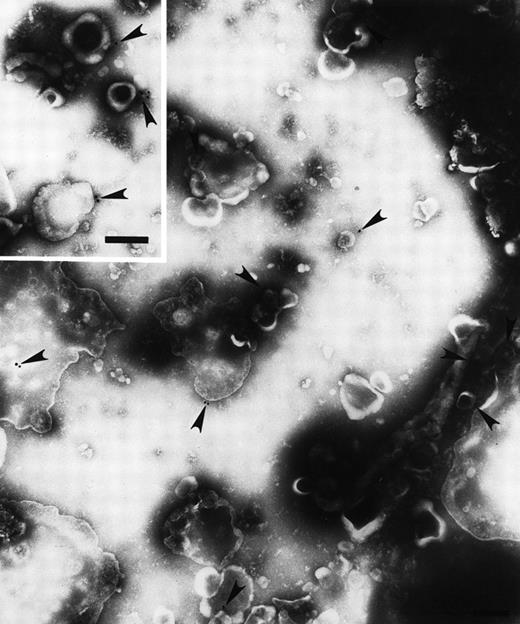

Plasma membrane-derived vesicles isolated from medium conditioned by CX-1 or MIP-101 cells were visualized by transmission electron microscopy, and Fas antigen was detected on their surface by immunogold particle labeling. Vesicle size and texture were heterogeneous, findings typical for shed vesicles.24 As shown in Figs 2 and3, vesicles from both cell lines are heterogeneous in shape and size (ranging from 0.05 to 0.5 μm) as well as in distribution of Fas (arrowheads) on the shed vesicle surface. No difference in vesicles released from MIP-101 versus CX-1 cells was apparent by electron microscopy. However, vesicles derived from CX-1 cells (Fig 3) show relatively less immunogold particle labeling than do vesicles shed from MIP-101 cells (Fig 2). The distribution of Fas on vesicles derived from plasma membranes of MIP-101 cells was typical for all fields that were examined. In contrast, vesicles shed from CX-1 cells failed to show the presence of Fas in the majority of fields that were examined.

Electron micrograph of immunogold-labeled Fas-bearing vesicles shed from MIP-101 cells. Fas (arrowheads) was detected with gold particle-conjugated antimouse anti-Fas antibody. The micrograph is at 57,000× magnification and the inset is at 68,000× magnification; scale bar = 0.2 μm.